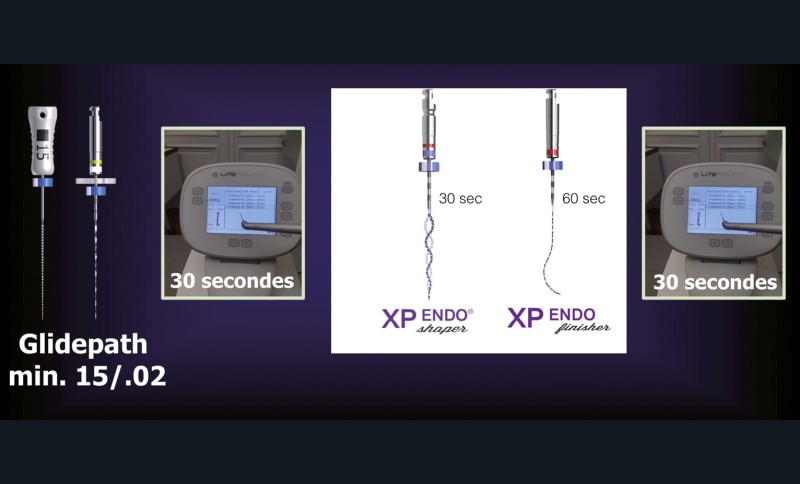

La faible efficacité pour la préparation et la mise en forme des canaux du laser Erbium requièrent une préparation canalaire mécanique.

Cet évasement canalaire a minima, dans le respect des parois canalaires, permet la progression et le renouvellement de l’irrigant dans les zones stratégiques de l’espace canalaire. Ce principe « mini-invasif » sera d’autant plus respecté par le bon choix d’instruments de préparation canalaire.

La nouvelle génération d’instruments en rotation continue, tels que le XP Shaper et le XP Finisher (FKG), s’inscrit parfaitement dans cet esprit, respectueux des parois radiculaires, tout en ayant un nettoyage optimal.

La deuxième séance consistera alors en l’élimination parfaite de l’OH2Ca sous irrigation avec l’Er:YAG [41] en association avec le XP Finisher [42] pour optimiser le nettoyage et la stérilisation du canal. Le XP Finisher étant par ailleurs indiqué dans la stimulation apicale et la formation d’un caillot, sans risque. Le caillot, ainsi formé, pourra être recouvert de Biodentine.

L’utilisation d’instruments en nickel titane, tels que le XP Shaper (FKG), le Vortex blue (Dentsply) ou le Profile (Dentsply), optimise la remontée des débris et s’inscrit dans cette nouvelle philosophie. En conséquence, la combinaison XP Shaper, XP Finisher et l’irrigation avec l’Er:YAG semblent optimiser nos traitements [44,45].

Le passage du laser est répété plusieurs fois, en début, au milieu et en fin de préparation. Un protocole peut alors être proposé : 40 mJ ; 20 Hz (fig. 7). L’utilisation de biocéramiques Bioroot (Septodont) ou Total Fill R (FKG) permet de sceller le système ainsi nettoyé, en assurant une action biologique de longue durée [46] (fig. 8a à c).